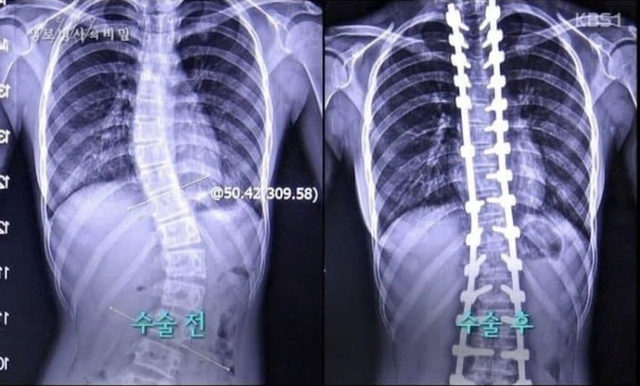

척추측만증으로 고생하는 여고생

저게 다 핀인가 ㄷㄷ

세자매 전부다 척추측만증

유전이라고 함 ㄷㄷ